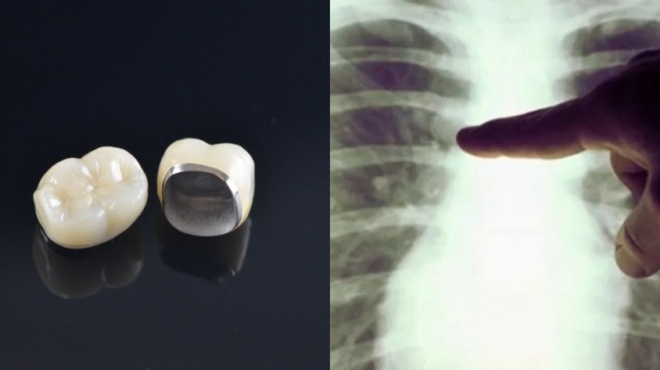

Θήκη δοντιού: Μία θήκη από δόντι σφηνώθηκε σε πνεύμονα από ασθενή. Το περιστατικό έλαβε χώρα κατά τη διάρκεια της διασωλήνωσης του ασθενούς στο νοσοκομείο της Λαμίας.

Θήκη από δόντι που είχε σφηνωθεί στον πνεύμονα ενός ασθενή κατά τη διασωλήνωση αφαιρέσαν γιατροί του νοσοκομείου Λαμίας. Αυτό έγινε με τη χρήση εύκαμπτου βρογχοσκοπίου και ειδικής λαβίδας. Ο ασθενής, ένας 50χρονος αλκοολικός και καπνιστής, είχε υποστεί ενδοεγκεφαλική αιμορραγία. Ο ίδιος εξαιτίας της πτώσης του επιπέδου συνείδησης είχε διασωληνωθεί στο Καρπενήσι. Εκεί, διακομίστηκε στο νοσοκομείο Λαμίας και αντιμετωπίστηκε στη ΜΕΘ και στο Βρογχολογικό Εργαστήριο της Πνευμονολογικής Κλινικής. Η νοσηλεία του διήρκησε μέχρι να βελτιωθεί η κατάστασή του και να πάρει εξιτήριο.

Όπως ανέφερε στο ΑΠΕ-ΜΠΕ ο επεμβατικός-πνευμονολόγος Εμμανουήλ Μάνος το περιστατικό αυτό αντιμετωπίστηκε το καλοκαίρι του 2020, όταν ο ασθενής διακομίστηκε διασωληνωμένος από το Καρπενήσι στη ΜΕΘ του νοσοκομείου Λαμίας. Κατά τη διάρκεια της νοσηλείας του στη ΜΕΘ παρουσίασε πνευμονία και εικόνα σηπτικής καταπληξίας και σε ακτινογραφία θώρακα φάνηκε ότι υπάρχει εισρόφηση ξένου σώματος που έμοιαζε με δόντι αλλά όπως αποδείχτηκε στη συνέχεια ήταν θήκη από δόντι που σφηνώθηκε στον δεξιό κάτω λοβαίο βρόγχο ως επιπλοκή της διασωλήνωσης.

Στη συνέχεια ο ασθενής υποβλήθηκε σε βρογχοσκόπηση με εύκαμπτο βρογχοσκόπιο μέσω τραχειοστομίας και με τη χρήση Rat’s teeth λαβίδας, αφαιρέθηκε η οδοντική θήκη η οποία απέφρασε την είσοδο του δεξιού κάτω λοβαίου βρόγχου και βρέθηκαν άφθονες πυώδεις εκκρίσεις και κοκκιώδης ιστός. Σε καλλιέργειες που έγιναν στη συνέχεια ο ασθενής βρέθηκε θετικός σε ακινετοβακτήριο, κλεμπσιέλλα και ψευδομονάδα.

Στην περίπτωσή μας, η εισρόφηση του ξένου σώματος έγινε πιο πιθανά, κατά τη διασωλήνωση ή τους ιατρικούς χειρισμούς στη νοσηλεία του. Η πιο συχνή θέση ενσφήνωσης αποτελεί ο δεξιός κάτω λοβός. Τα συμπτώματα περιλαμβάνουν παραγωγικό βήχα, δύσπνοια ή παρατεινόμενο εμπύρετο. Η ακτινογραφία θώρακα αναδεικνύει το ξένο σώμα, εφόσον είναι μεταλλικό, ή θα αναδειχθεί πύκνωση, ατελεκτασία ή φυσιολογική ακτινογραφία. Η αφαίρεση πραγματοποιείται συνήθως βρογχοσκοπικά, κυρίως με εύκαμπτο βρογχοσκόπιο».